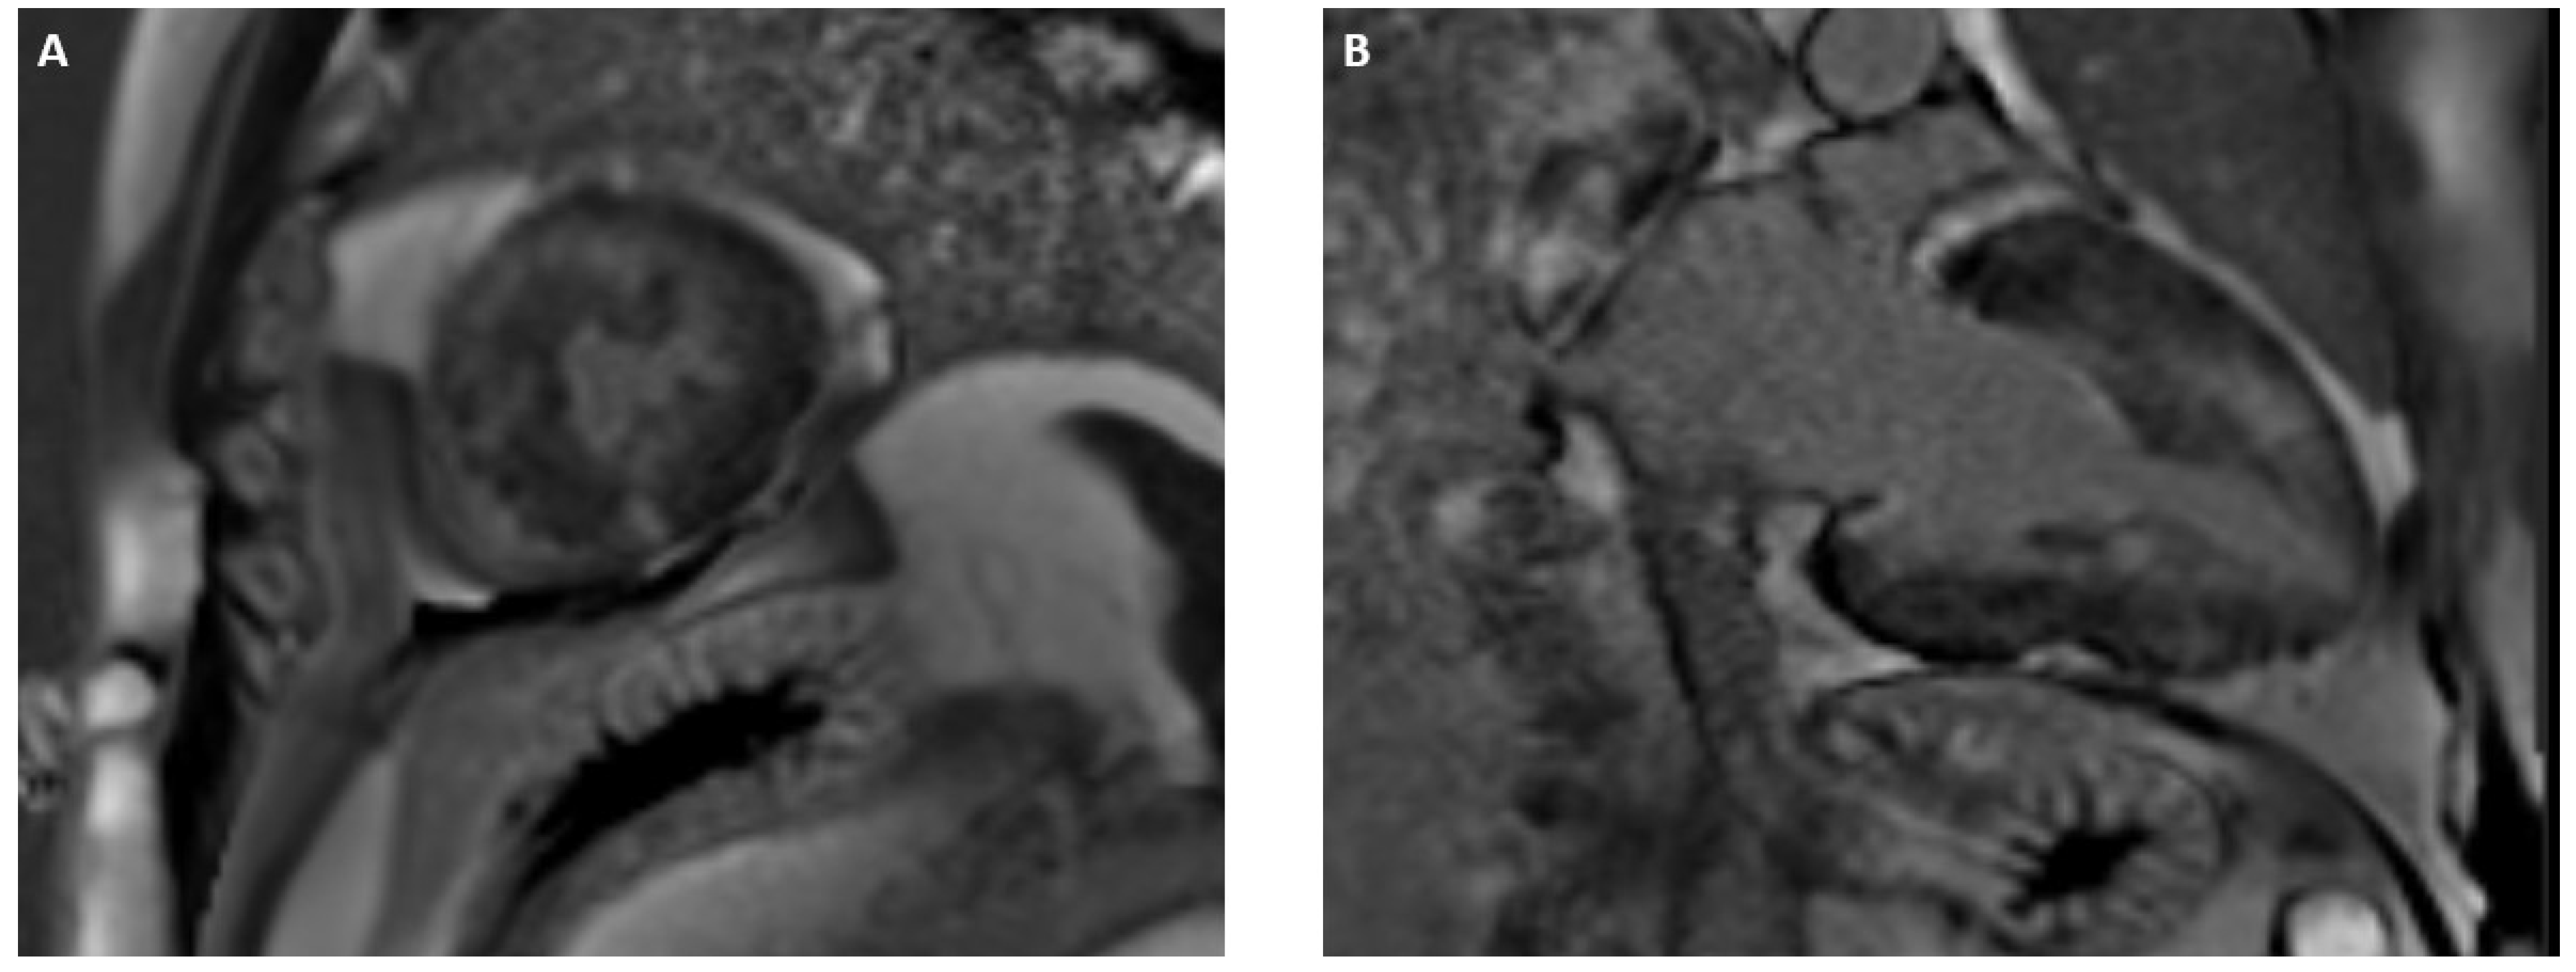

3.2. Acute Myocarditis

3.3. Chemotherapy-Induced Cardiotoxicity